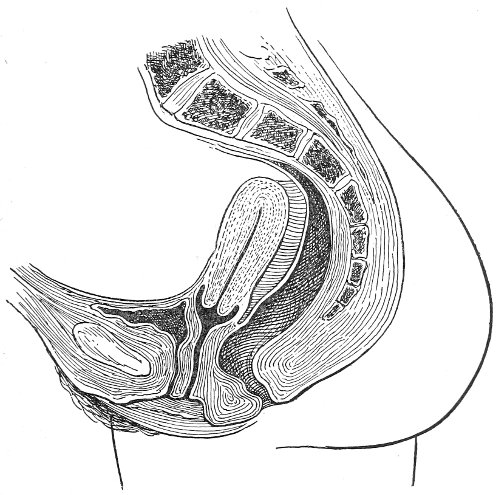

Fig. 3.—Bimanual examination; median sagittal section of the pelvis.

Vaginal and Bimanual Examination.—Having examined and noted the condition of the external genitals, the physician should next proceed to examine the vagina. The index finger of the right or the left hand should be gently introduced into the vagina. The condition of the vaginal walls, and the direction, consistency, form, etc. of the vaginal cervix, may be determined. The shape and size of the os uteri should be noted. The ulnar edge and the tips of the fingers of the other hand should then be placed upon the abdomen, immediately above the symphysis pubis, and gently pressed backward and downward toward the vaginal finger 24 (Fig. 2). In this way the various pelvic organs, the uterus, Fallopian tubes, ovaries, and ureters, may be palpated between the two hands, and their position, size, shape, and consistency may be determined. Such an examination is, of course, made much more easily in a thin woman than in a fat one. A thin woman a few weeks after labor may be examined most easily, on account of the relaxation of the abdominal and vaginal walls.

In making the bimanual examination the structures 25 should be palpated methodically in order. The vaginal finger notes the condition of the cervix uteri. If the fundus be in the normal position, the uterus can then be taken between the abdominal hand (upon the fundus) and the vaginal finger (upon the cervix) (Fig. 3). The shape, size, mobility, and consistency are noted. The vaginal finger is then passed anteriorly and laterally toward either uterine cornu, while the abdominal fingers pass over to the posterior aspect of the same cornu. The ovarian ligament and the proximal end of the Fallopian tube may thus be felt. Passing farther outward, the whole of the tube and the ovary may be examined. The same procedure is then applied to the opposite side.